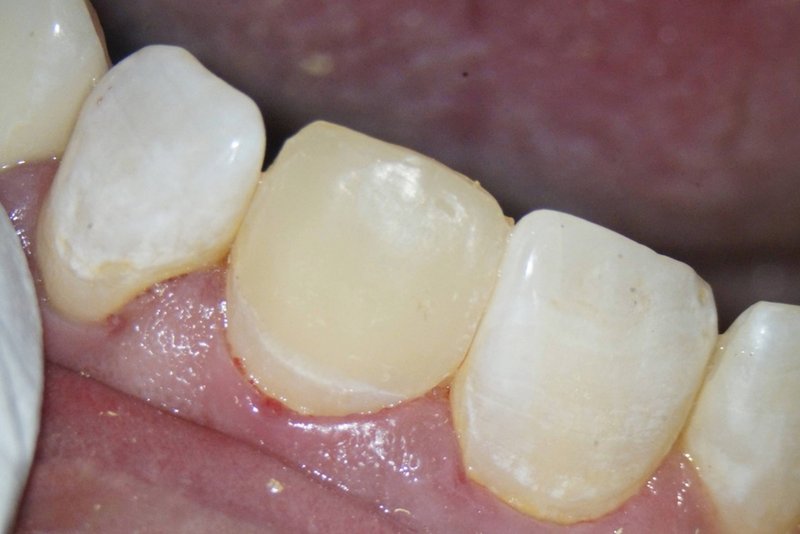

Kronenfraktur: Zustand vor der Wurzelkanalbehandlung